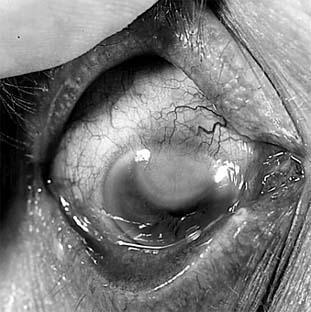

Fungal ulcers are indolent and have a gray infiltrate, often a hypopyon, marked inflammation of the globe, superficial ulceration, and satellite lesions (usually infiltrates at sites distant from the main area of ulceration) (Figure 6-3). The principal lesion-and often the satellite lesions as well-is an endothelial plaque with irregular edges underlying the principal corneal lesions, associated with a severe anterior chamber reaction and a corneal abscess.

Figure 6-3

Figure 6-3: Corneal ulcer caused by Candida albicans.

Most fungal ulcers are caused by opportunists such as Candida, Fusarium, Aspergillus, Penicillium, Cephalosporium, and others. There are no identifying features that help to differentiate one type of fungal ulcer from another.

Scrapings from fungal corneal ulcers, except those caused by Candida, contain hyphal elements; scrapings from Candida ulcers usually contain pseudohyphae or yeast forms that show characteristic budding. Tables 6-2 and 6-3 list the drugs recommended for the treatment of fungal ulcers.